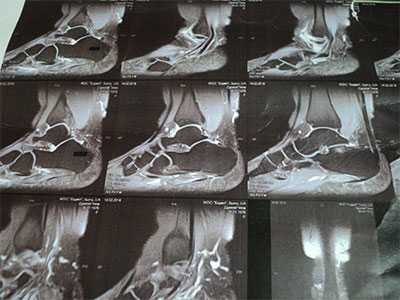

МРТ при импиджмент-синдроме заднего отдела голеностопного сустава

Визуализация

УЗИ, рентгенография, КТ, МРТ, артроскопия

МРТ голеностопного сустава